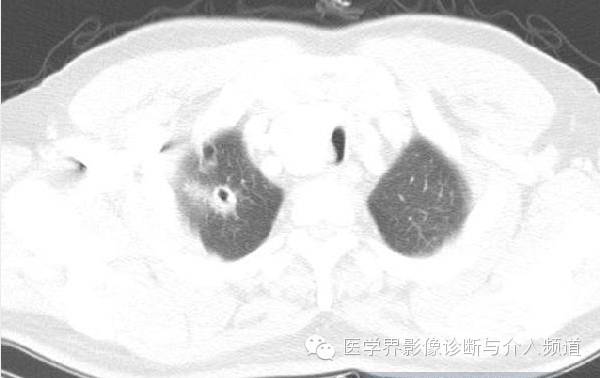

治疗前

CT显示右肺上叶实性团块病灶内不规则空洞形成,周围可见GGO,右侧胸腔少量积液。患者外周血嗜酸性粒细胞增多和Pw抗体阳性。治疗后X线平片显示右上肺结节影缩小。治疗前X线片显示病灶位于右肺上野,右侧肋膈角变钝。此外,X线平片示主支气管节段性偏心性狭窄,这是由于胸内甲状腺肿外在压迫所造成。